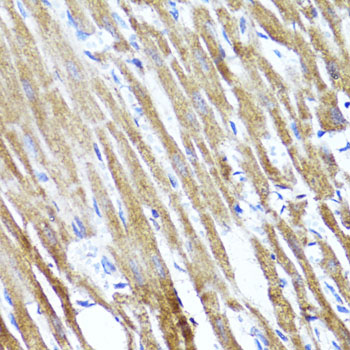

Inhibits cytokine signal transduction by binding to tyrosine kinase receptors including gp130, LIF, erythropoietin, insulin, IL12, GCSF and leptin receptors. Binding to JAK2 inhibits its kinase activity.

| Gene Name: | SOCS3 |

Widely expressed with high expression in heart, placenta, skeletal muscle, peripheral blood leukocytes, fetal and adult lung, and fetal liver and kidney. Lower levels in thymus.